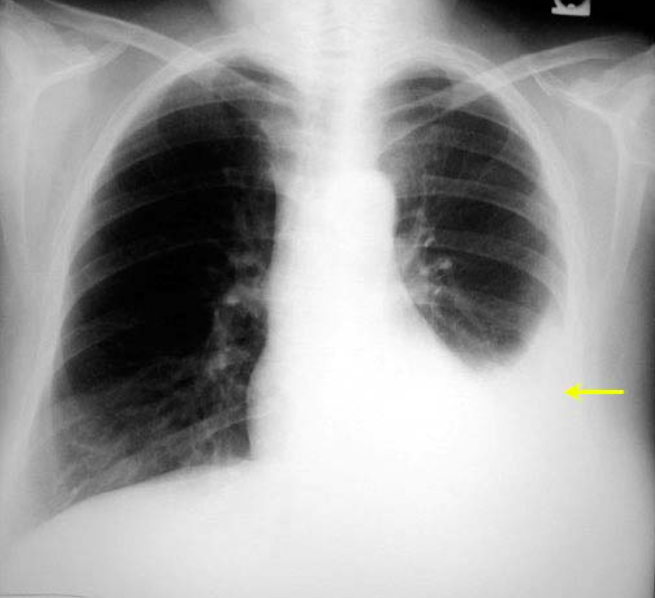

What can be seen in this image?

Pleural Effusion